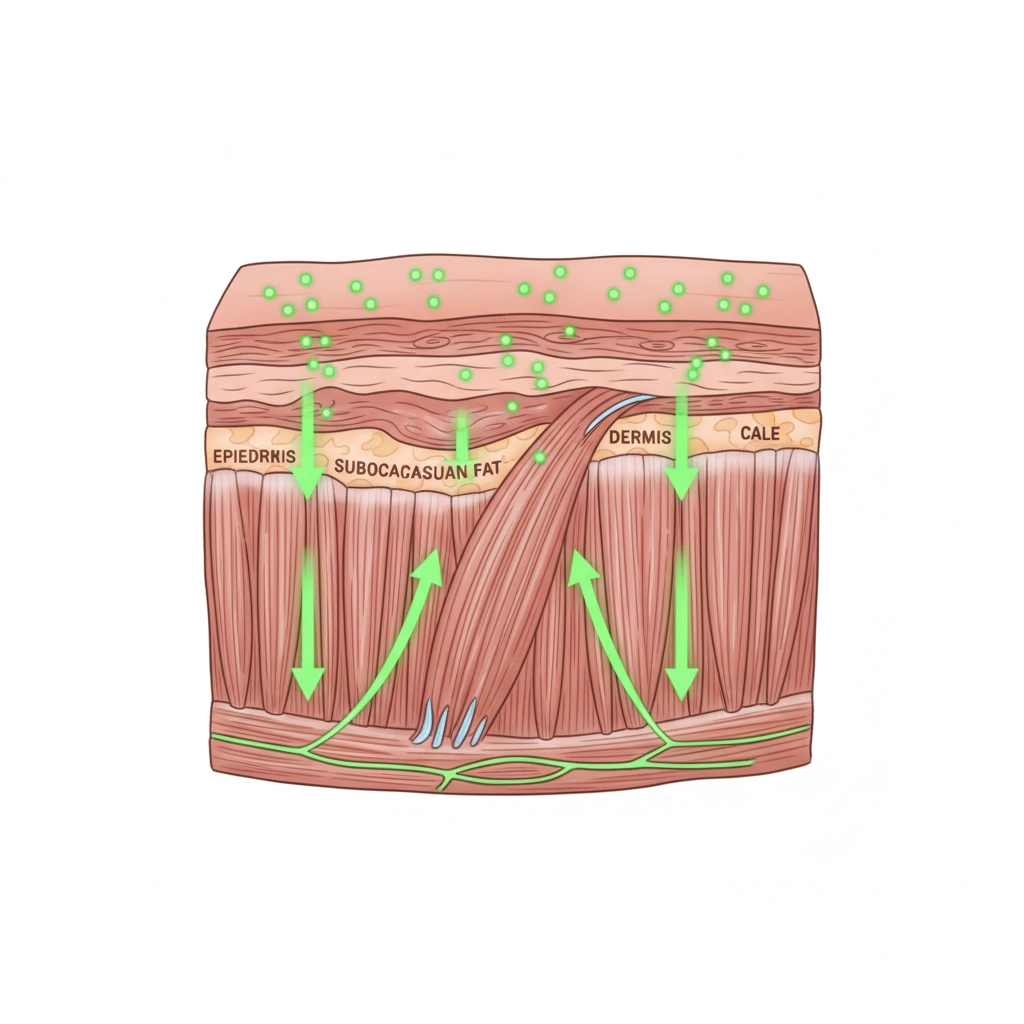

What makes Clayer different? Our French Green Clay contains over 75 trace minerals that work synergistically to:

✅ ACCELERATE TISSUE REPAIR through enhanced mineral absorption

✅ IMPROVE CIRCULATION instead of restricting it

- Promotes healthy blood flow

- Delivers essential minerals to injury site

- Supports cellular regeneration